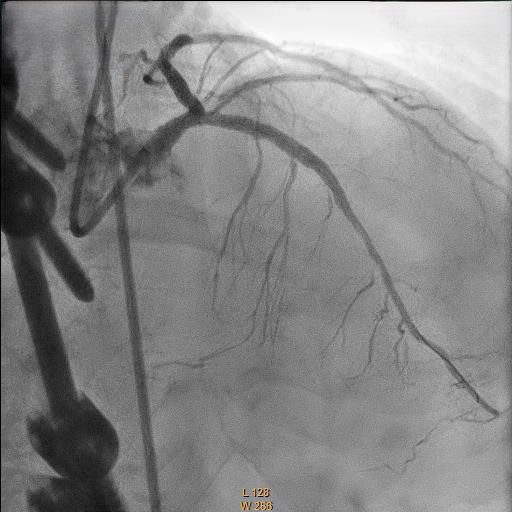

Relevant Catheterization Findings

Coronary angiography showed 50% stenosis at Left Main (LM), proximal to mid Left Anterior Descending Artery (LAD) 70% stenosis, 80% stenosis at mid Left Circumflex Artery (LCX) and Chronic Total Occlusion at mid Right Coronary Artery (RCA) with collateral from LAD.

Right femoral artery punctured approach by 7Fr femoral sheath. Coronary guide catheter EBU 3.5 was used to engage left coronary artery. Percutaneous Coronary Intervention (PCI) to bifurcation Medina 1,1,1 using T and small protrusion (TAP) technique. LAD and LCX wired with workhorse wire . Mid LAD predilated with Semi-compliant (SC)2.5mm balloon and proximal LAD predilated with non-compliance (NC) 3.5mmballoon. Intravascular Ultrasound ( IVUS) was performed to measure the vessel size, lesion length and plaque morphology. Mid LAD stented with 3.5x23 mm drug eluting stent (DES). LM until proximal LAD stented with 4x33mm DES . Proximal optimization therapy (POT) at LM with NC balloon 5x8mm. Proximal LAD post dilated with NC balloon 4x20mm and mid LAD post dilated with NC balloon 3.5x15mm. LCX rewired with workhorse wire. Ostial LCX predilated with NC balloon 3.5x15mm and stented with 3.5x23mm DES subsequently post dilated with NC balloon 3.75x20mm. Final kissing balloon inflation was done at ostial LAD using NC balloon 4.0 and ostial LCX using NC balloon 3.75. Final IVUS noted double barrel sign at LM stent and confirmed with stent enhancement likely due to abluminal side branch wiring. Final POT to LM with NC balloon 5x8mm. Final IVUS showed good stent expansion and opposition with no dissection.